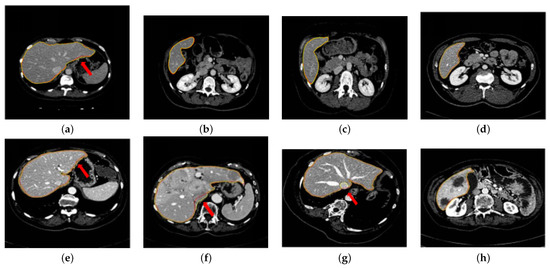

To show the effectiveness of the proposed method, we select some representative abdominal CT images with different shapes, angles, positions, and slice thicknesses for segmentation from 55 CT sequences. Figure 6a–d show the abdominal CT liver segmentation results of our method in the case of no lesions or minor lesions. Figure 6e–h show our method’s segmentation results under the condition of serious lesions. In some of these images, the liver even has obvious lesions, such as (h). The yellow contour represents the segmentation results of the proposed method in abdominal CT, and the red contour represents the results of manual segmentation by experts. We can find that, whether there are lesions or not and whether the shape of the liver changes, the extracted liver region is consistent with that given by experts.

Figure 6.

Representative choice of liver segmentation results by the proposed method: (a–d) show the images in the case of no lesions or minor lesions; (e–h) show the images under the condition of serious lesions.